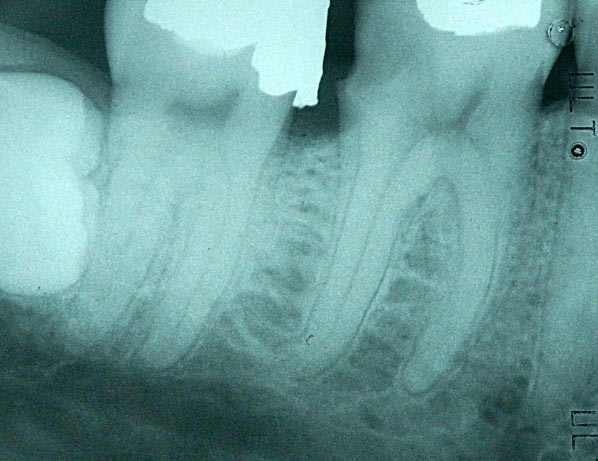

Tiens en parlant d'honneur la je meriterais un grand doigt.

Protaper dans la racine mesiale, amlg dans la racine distale, Mais j'ai mis la digue :p.

Conclusion RAS au controle a 1 an !

Comme dit Stéphane tous les moyens sont bons tant qu on arrive au résultat escompté ;p